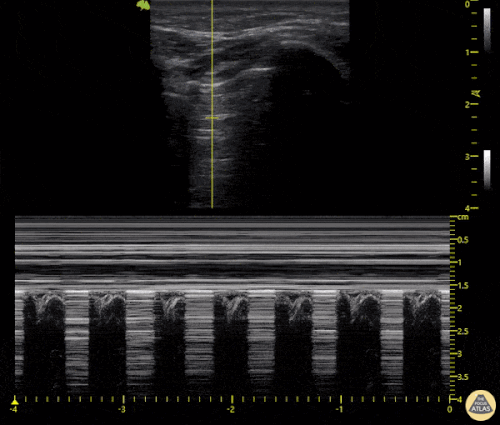

M-mode kullanımı

Pnömotoraks değerlendirmesinde M-mode da kullanılabilir.

Aynı pencerede M-mode kaydı alınır:

-

Lung sliding varsa (pnömotoraks yoksa)

Plevral hat seviyesinde belirgin bir ayrım görülür ve bu görünüm “seashore sign” (kumsal belirtisi) olarak adlandırılır.